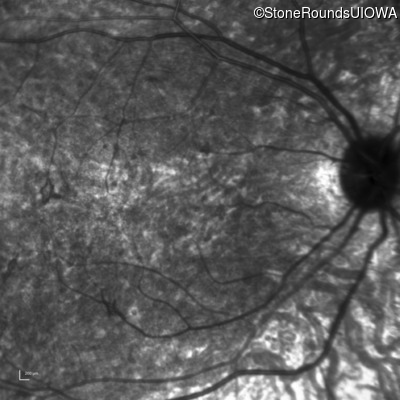

Age at visit: 8 years (Visit 2)

Age at visit: 9 years